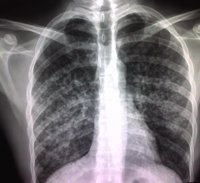

1. ¿Qué es la tuberculosis?

La tuberculosis es una enfermedad infecciosa transmisible causada por una bacteria 'Mycobacterium tuberculosis', si bien puede estar causada por otras bacterias semejantes ('Mycobacterium bovis', 'Mycobacterium africanum'), con las que forma el denominado 'Complejo Mycobacterium tuberculosis'. Afecta esencialmente al aparato respiratorio, donde produce la destrucción de los tejidos pulmonares, aunque, puede afectar a cualquier órgano del cuerpo.